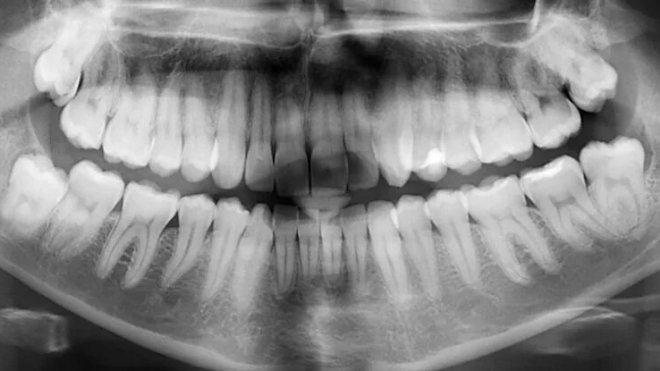

Жизненный путь человеческих зубов делится на два принципиально разных этапа. Изначально, пока зуб еще находится внутри десны и не вылез на смену молочному, в нем полно жизни. В частности клетки-амелобласты выделяют особые белки, которые и формируют эмаль зуба. Но когда сформированный зуб оказывается снаружи, амелобласты отмирают, активность прекращается, а эмаль начинает постепенно разрушаться под воздействием ряда факторов.

Природа не предусмотрела механизма восстановления зубов или хотя бы эмали, они предоставлены сами себе, и только тщательная гигиена полости рта как-то защищает их. Американские ученые изучили белки, которые создают эмаль, и создали их пептидный аналог, который выполняет только одну функцию – запускает процесс минерализации вещества. Эмаль постепенно восстанавливается, как если бы зуб вдруг «ожил» и решил отремонтировать сам себя.

Из-за того, что в искусственном пептиде нет ничего лишнего, его влияние на зуб и среду во рту строго ограничено, это безопасное средство. Его можно наносить на зубы в виде пасты или геля, и применять без рецепта врача. Увы, это средство только для восстановления поверхности эмали, глубокие повреждения, как и проблемы с дентином под ней, так вылечить не получится. Скорее, оно станет профилактическим средством, которое нужно будет применять вместе с обычной зубной пастой.